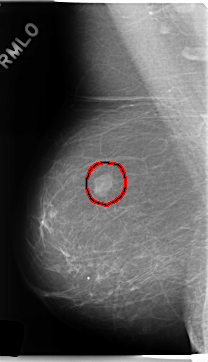

C_0249_1.RIGHT_MLO

LESION_TYPE MASS SHAPE LOBULATED MARGINS CIRCUMSCRIBED

ASSESSMENT 4

SUBTLETY 5

PATHOLOGY BENIGN